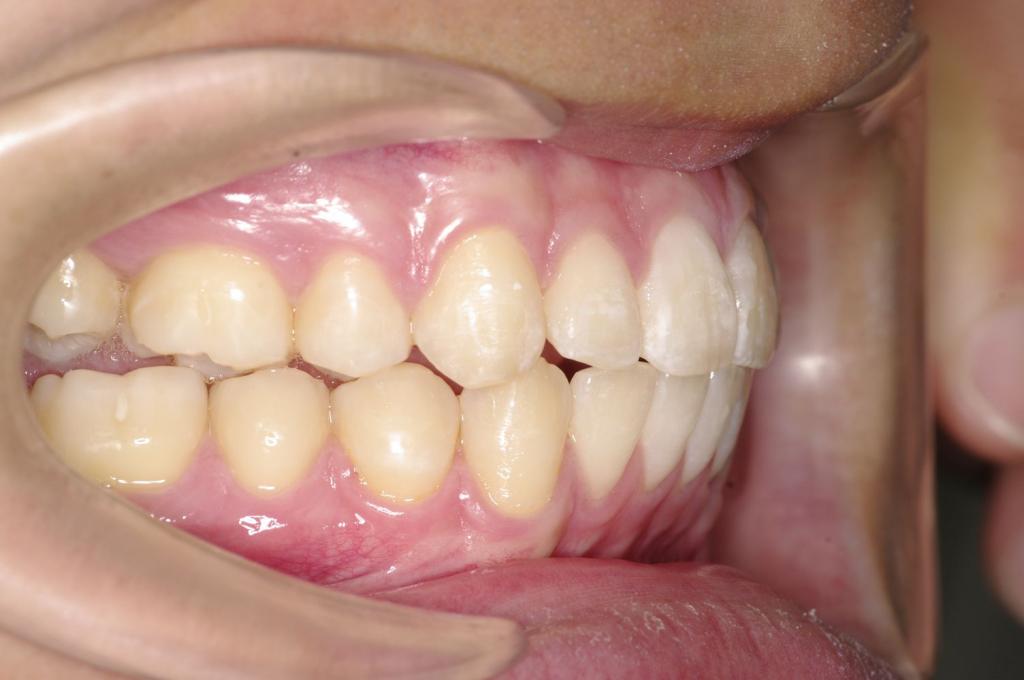

前歯、出っ歯・開咬の矯正治療

(治療期間、治療前後写真、治療方法、費用)WORKS